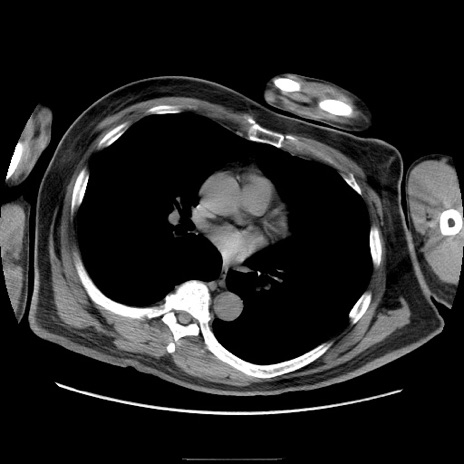

【症例】50歳代男性

【主訴】腹痛

【現病歴】AVMからの被殻出血のため回復期リハ病棟入院中。 本日午後3時頃急に下腹部痛が出現した。

【既往歴】AVM、被殻出血、虫垂炎、高血圧

【身体所見】意識晴明、左半身不全麻痺、会話の理解は良好、36.5°C、腹部:膨隆、全体に板状硬、下腹部正中に圧痛点あり、反跳痛-、筋性防御不明、右下腹部にope scar

【データ】WBC 9400、CRP 0.06